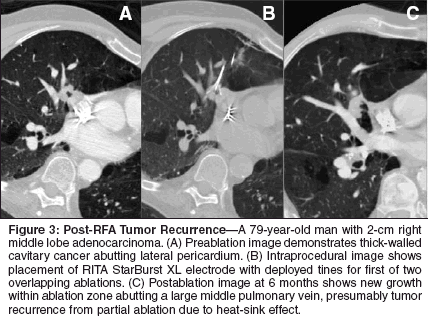

Complications have been reported in up to 76% of patients, most of them minor postablation-type symptoms, pneumothoraces, and pleural effusions. Pneumothorax rates have ranged from 4.2% to 53.8%, and those requiring evacuation with pleural catheter or thoracostomy tube from 7.2% to 25%. The occurrence of pleural effusions has been reported as 3.7% to 52.4%. Other complications have been sporadically reported with incidence rates at 10% or less. At least three deaths have been reported, the first due to lethal pulmonary hemorrhage in a patient on a commonly used antiplatelet drug, clopidogrel (Plavix),[37] the second related to Acute Respiratory Distress Syndrome 4 days following the RF procedure,[21] and the third as result of hemoptysis 19 days following RFA of a central tumor.[19] Imaging Follow-Up Reliable imaging is essential for RF ablation to become widely used in the treatment of lung tumors, not only for following tumor regression and postablation coagulation involution but to discern incompletely ablated or recurrent tumor within the ablation zone. Unfortunately, ablation zone size and morphology at conventional CT may not always be useful indices of ablation efficacy. For postablation follow-up, the larger reported patient series have used contrast-enhanced CT, including CT contrast nodule densitometry, positron emission tomography (PET) and PET/CT, and magnetic resonance. Contrast-enhanced CT has been the most widely used and studied. Parameters vary from one series to the next in collimation and timing of image acquisition, rate and volume of administered intravenous contrast, and imaging characteristics suggestive of efficacy. Most authors advocate a pretreatment scan followed by postablation scans at varying time intervals, usually every 3 to 6 months beginning around 1 month and continuing through 12 months. Some authors have scanned postablation patients as early as 1 day and 1 week postprocedure. Immediately following ablation, nonenhanced CT usually shows slightly increased attenuation along the electrode tract and decreased attenuation of the treated tumor, with enveloping ground-glass attenuation. Lee et al considers the thickness and pattern of ground-glass on initial imaging at one day useful in predicting treatment success. All eight tumors in which the ground-glass completely surrounded the treated tumor and extended more than 5 mm beyond the original tumor margins avoided local recurrence at a mean 22.2 months follow-up.[21] During and shortly after ablation, the opacification associated with ablation has been described as light bulb-shaped, surrounding both the electrode and tumor.[43] Gadaleta et al coined the colorful term "cockade phenomenon" to describe the multiple concentric rings with varying densitometric characteristics that appear in the parenchyma surrounding the lesion after 48 to 72 hours, because of their resemblance to a bow made of ribbon historically worn on berets.[24] This group also described clear sectorial hyperemia surrounding the lesion, or conical consolidation with its apex at the hilus lasting 24 to 72 hours.[24] Despite varying CT appearances, ablation zones will be largest immediately or approximately 1 week following ablation and will subsequently decrease over time (Figure 2). Treating metastatic colon carcinoma to the lung, Steinke et al demonstrated that at 1 week almost 100% of treated lesions were larger than baseline, at 1 month 95%, 3 months 76%, and 6 months 47%.[43] Jin et al showed similar decreases over time in the ablation zone, which decreased more than 40% after 1 year of follow-up.[35] Continued enlargement, particularly beyond 6 months, was consistent with partial ablation (Figure 3). Cavitation within the ablation zone seems to be a frequent and uneventful occurrence that may or may not resolve over the course of follow-up.[31] Features of the ablation zone on enhanced CT have also been described. Lee et al defined tumor necrosis as complete when the nonenhancing area at the treatment site had a diameter greater than or equal to that of the initially viable tumor, with no residual portion of the lesion enhancing more than 10 HU after contrast administration.[21] Following RFA of complete and even incompletely ablated tumor, a thin rim, usually less than 5 mm in thickness, can be seen along the circumference of the ablation zone. This benign periablational enhancement,[42] lasting up to 6 months, represents a benign physiologic response to thermal injury, initially from reactive hyperemia and subsequently from fibrosis and giant cell reaction. Both the pattern and appearance of increasing contrast enhancement may serve as useful indicators of incomplete tumor ablation or tumor recurrence within the ablation zone. Irregular peripheral enhancement, referring to scattered, nodular, or eccentric patterns of contrast enhancement within or immediately around the ablation zone, is best seen on delayed imaging during the venous phase (> 180 seconds after contrast injection) and represents residual or recurrent tumor (Figure 4).[42] Irrespective of enhancement pattern, mean contrast uptake substantially decreases within the first 1 to 2 months postablation. In most instances, the appearance of abnormal enhancement first occurs at approximately 3 months and indicates the presence of recurrent disease.[20]